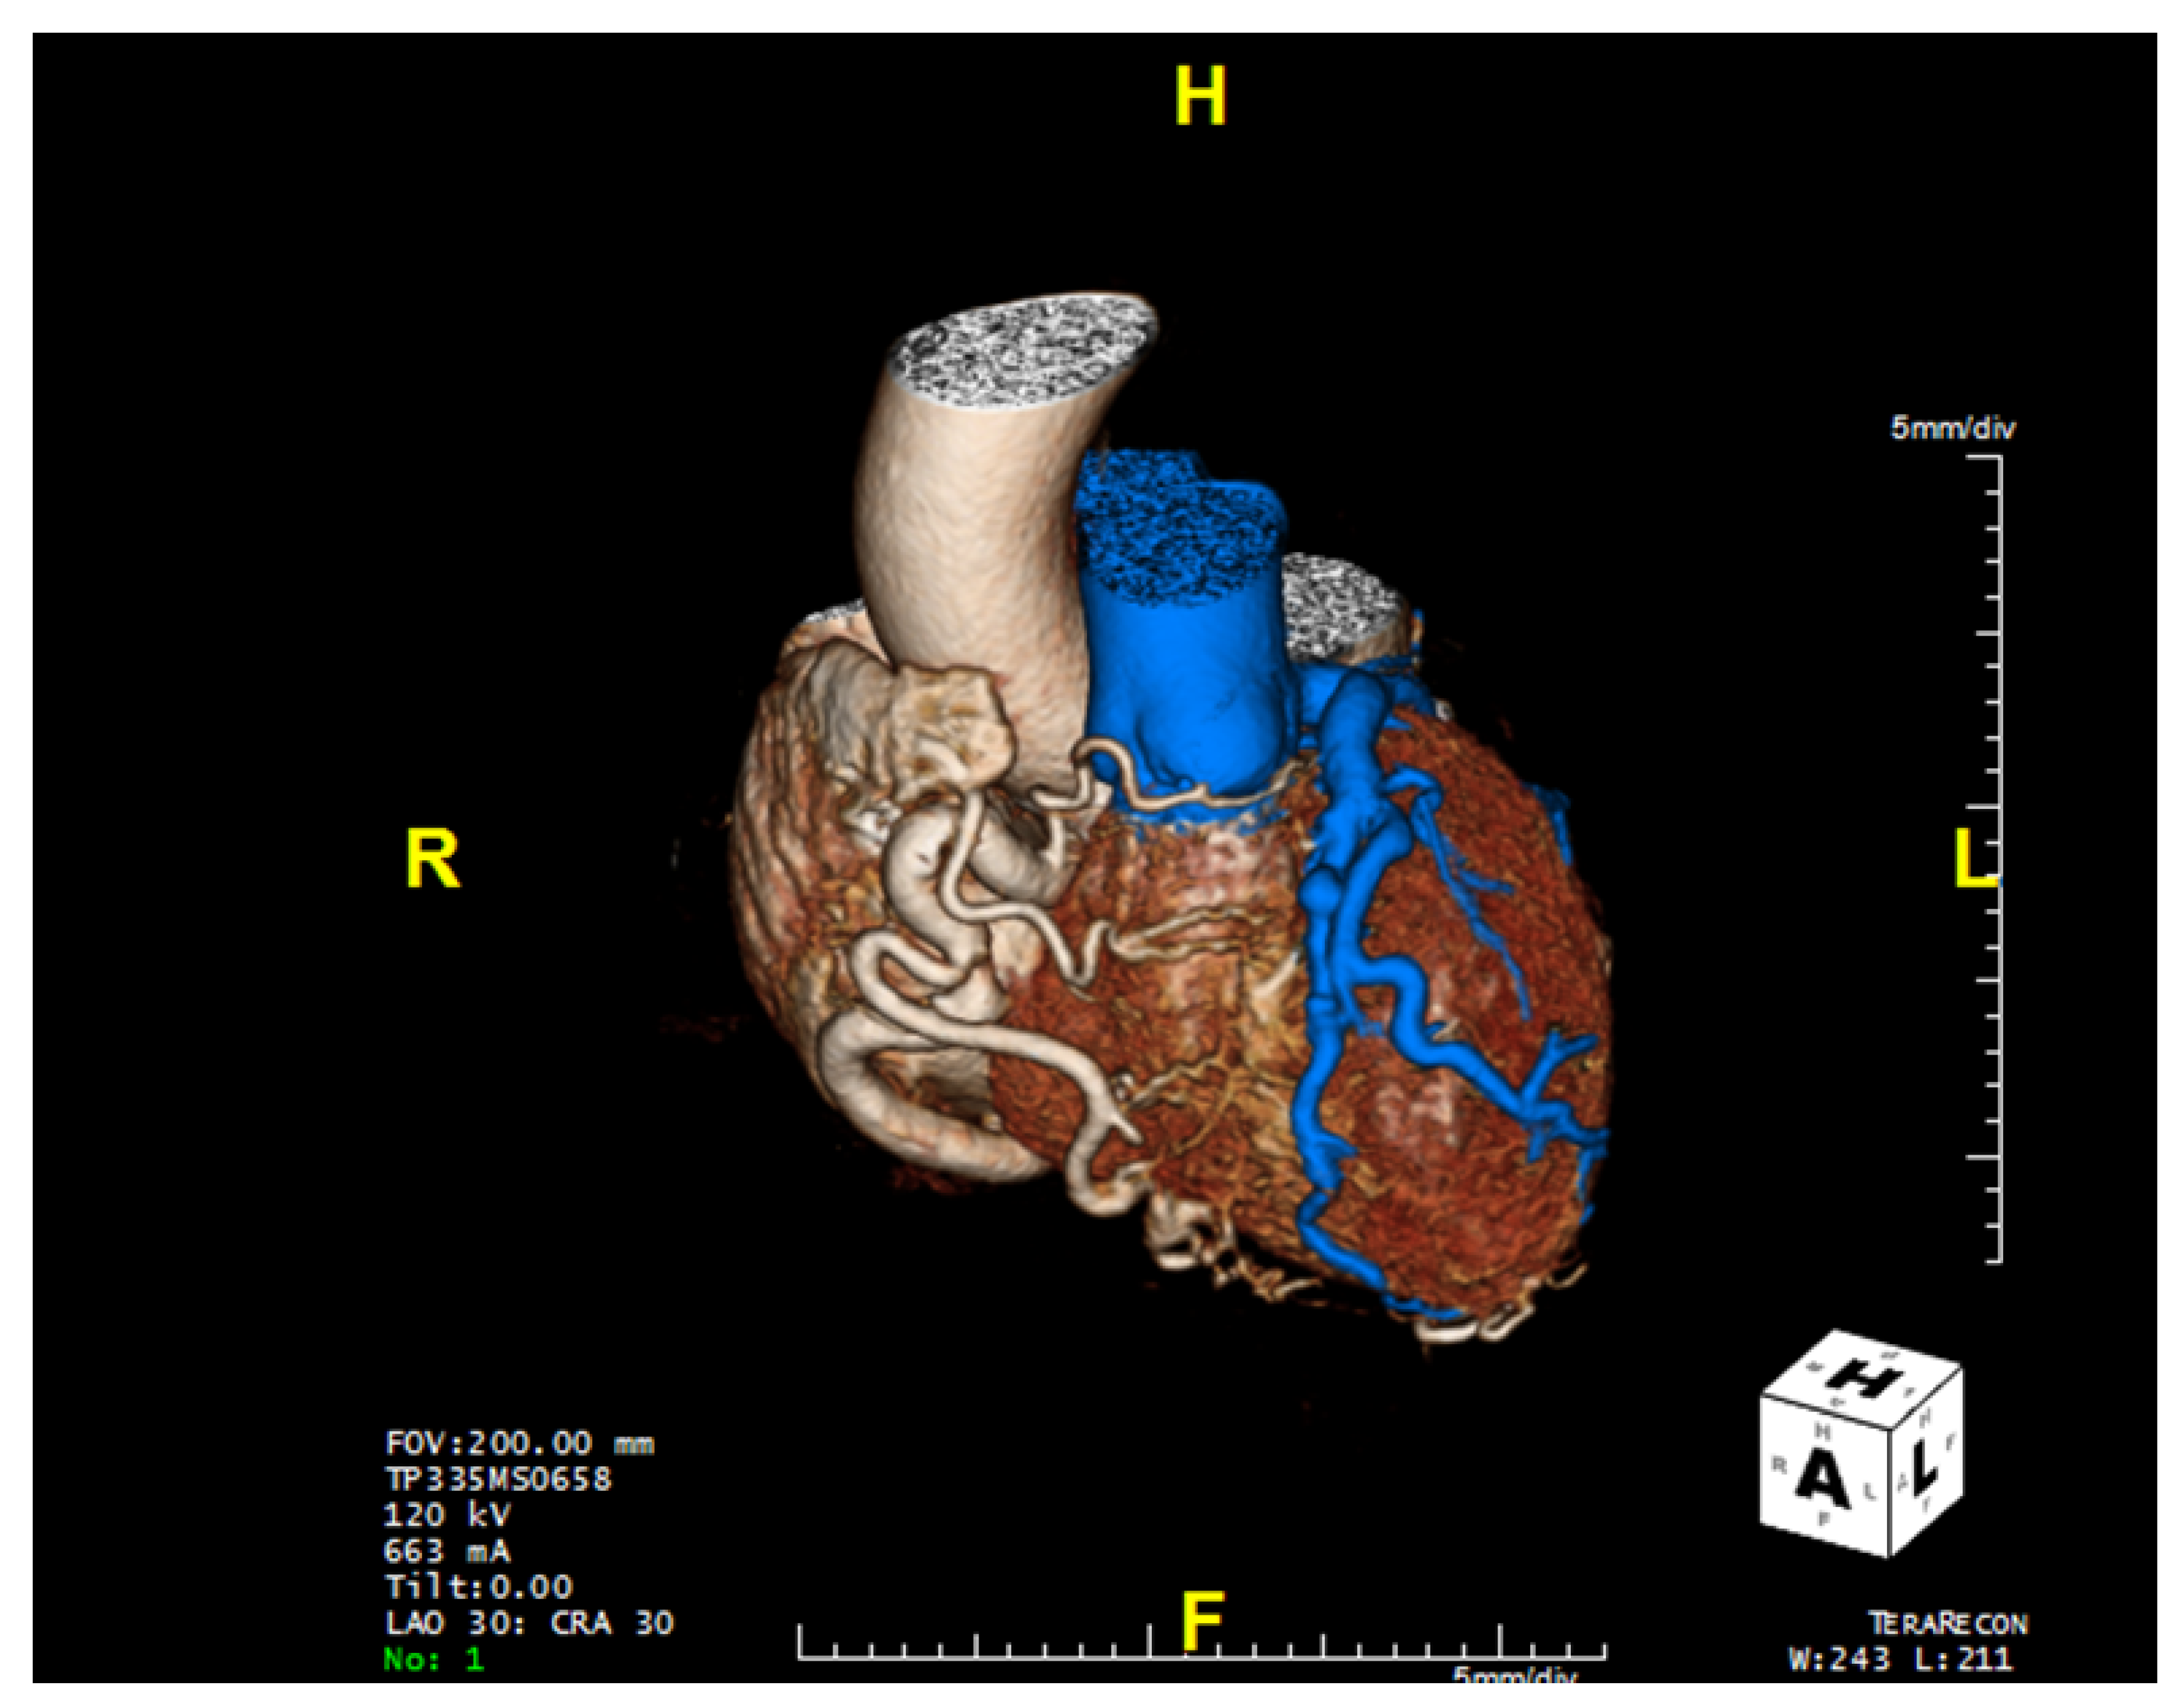

Computed tomographic angiography provides superior visualization of the coronary arteries and can be used for the definitive diagnosis of ALCAPA (Table 1), anatomic assessment, and postoperative follow-up. When CTA is utilized (Figure 5), direct visualization of the left coronary artery originating from the pulmonary artery, a dilated right coronary artery with extensive coronary collateral arteries, abnormal left ventricular wall movement, and dilated bronchial arteries—which act as systemic collaterals—denote ALCAPA [7]. In ALCAPA, the left coronary artery arises from the left inferolateral aspect of the main pulmonary artery just after the pulmonary valve and courses toward the interventricular groove before branching into the left anterior descending artery and the left circumflex artery. In infants, the right and left coronary arteries may appear normal. However, the coronary arteries are dilated and tortuous in adults, with dilated intercoronary collateral arteries coursing along the epicardial surface of the heart or within the interventricular septum [7].

Figure 5. Computed tomography of the heart revealing anomalous left coronary artery from the pulmonary artery (blue) as well as the dilated and tortuous right coronary artery.